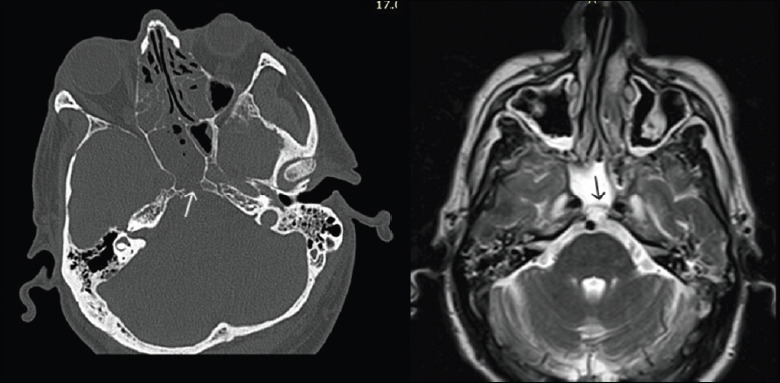

Background: Ecchordosis physaliphora (EP) is a benign hamartomatous lesion, most commonly found in a retroclival position, as an incidental radiological finding. EP may become symptomatic, by creating a clival defect, leading to CSF leak and meningitis, thus requiring surgical treatment.

Results: We present 5 cases of retroclival EP (4 males, 1 female; age range, 34-81 years) presenting in our department over the last 6 years. Four patients presented with CSF leak; 3 also had a history of bacterial meningitis, while one was diagnosed with meningitis on presentation. One patient was and remains asymptomatic 28 months later with the lesion being an incidental finding. The EP was treated in all 4 symptomatic patients with removal of the lesion and reconstruction of the defect with an endoscopic endonasal transclival approach (EETTA). All 4 patients remain free of symptoms while the lesion has not recurred for 81, 72, 52, and 22 months, respectively.